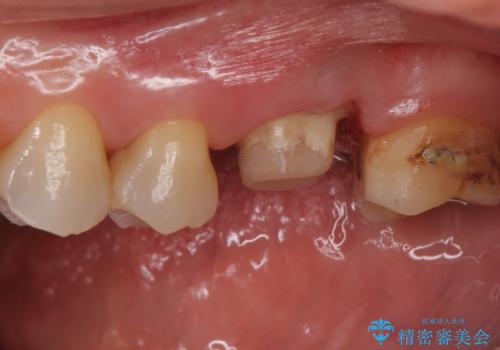

- 検査の結果被せ物の下に虫歯が確認された患者様です。

虫歯を取りきった後セラミッククラウンでの修復処置を行います。

- 左上6/仮歯+ジルコニアクラウン:11,000円+110,000円 (根管治療:保険)費用は治療当時の料金となります

被せ物の裏側の虫歯は被せ物を取らないと除去できません。

今回は過去に治療された部分をすべてやり直しました。